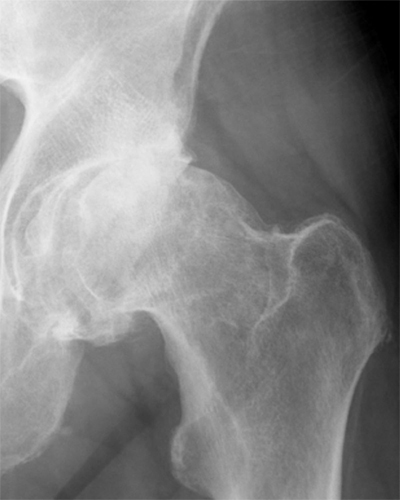

Coxarthrose

Die Arthrose ist eine Erkrankung des Gelenkes, bei der die knorpeltragende Schicht zunehmend dünner wird, bis in einem fortgeschrittenen Stadium ein unmittelbarer Knochenkontakt zwischen Hüftkopf und Pfanne besteht.